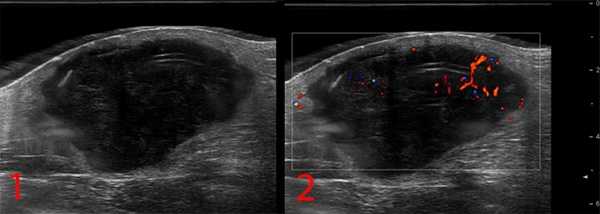

— УЗИ опухолей мягких тканей. Это метод диагностики как первичного очага, так и поражения региональных зон. Позволяет определить границы опухоли, связь с окружающими органами, структуру опухоли;

Рисунок №1. Саркома мягких тканей бедра. УЗ-картина в серошкальном и сосудистом режимах визуализации